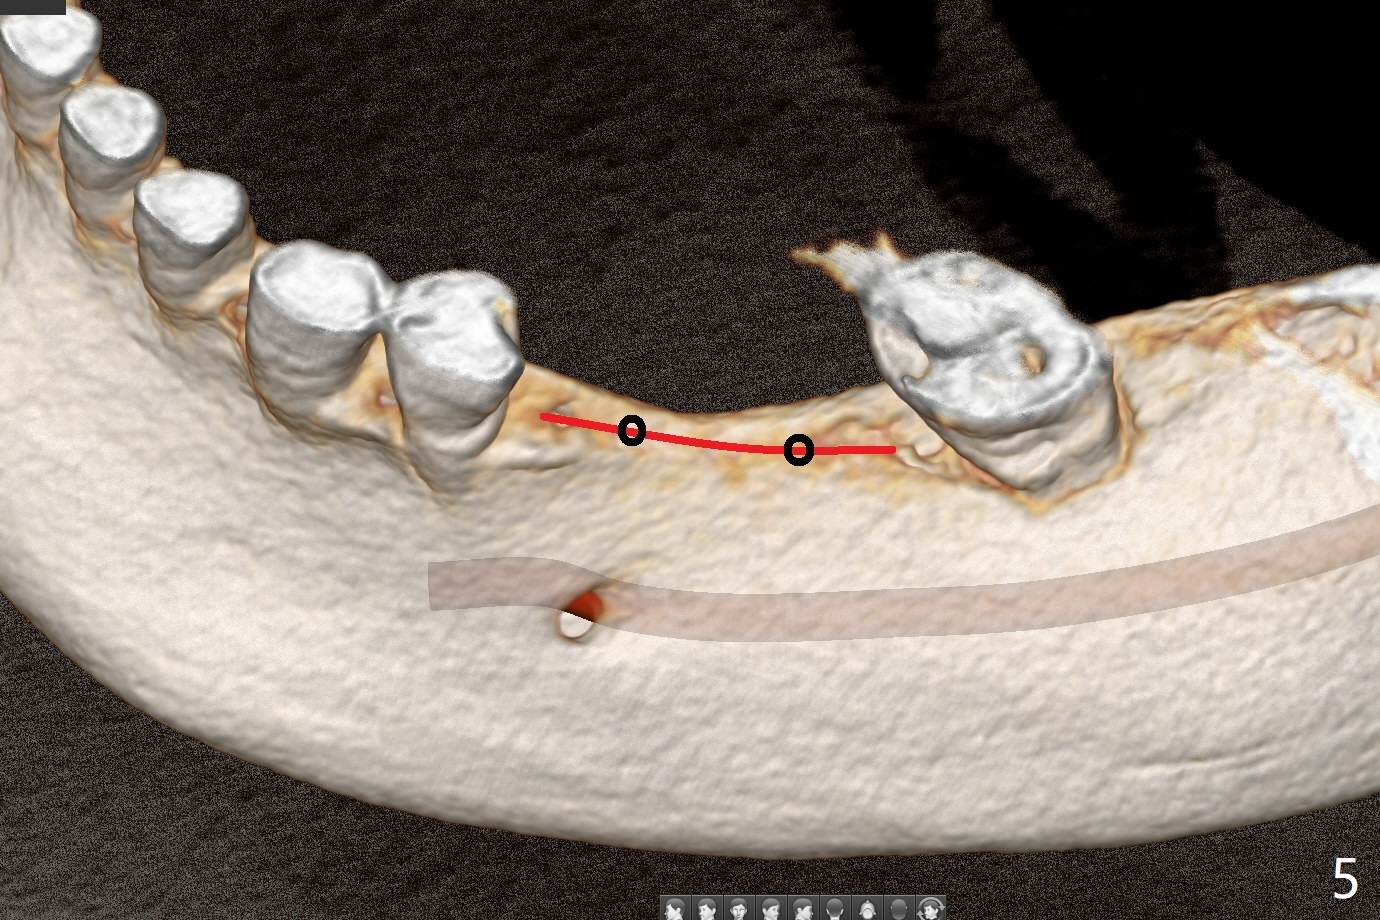

57岁女缺失四个下牙(图一),由于保险限制,先考虑左边种植(图二,三),主要问题是牙槽嵴狭窄(不过左上牙桥做的太长了,尤其是5,6(图一'),造成下面垂直距离缩短,修复困难。总之,她的牙齿显得短小)。牙槽嵴狭窄处理方法:切口,使用导板用bone trimmer和最细钻头(point drill或者2.2毫米)钻洞(图四:黑圆圈),到深度,然后用圆形骨锯在牙槽嵴顶部劈开(弯曲红线),必要时做三个垂直骨切口(图六),徒手利用旋转式骨扩张器,或者骨凿,推开颊侧骨板。也准备外科钻头(新的)。放置导板和钻头除去舌侧骨板,最后在5,6分别植入3.0 或者3.5毫米,4.0或者4.5毫米植体。如果初步稳定性好,即刻修复,主要防止7继续近中倾斜,必要时,7近中(图一*)植骨。抽血制备两个PRF膜和粘性骨块。